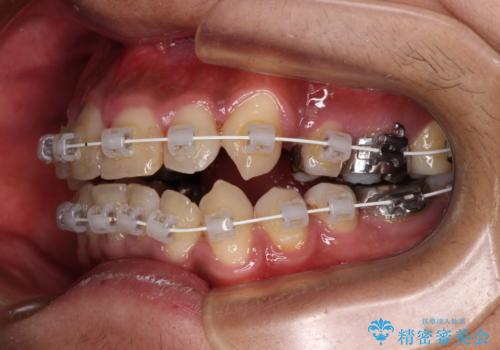

八重歯と開咬 ワイヤー装置での抜歯矯正

- 前歯のデコボコと八重歯、開咬を気にして来院された患者様です。

骨格的に下顎骨が上顎骨に対して後退位であったため、上顎の左右第一小臼歯を抜歯し、デコボコを改善するとともに開咬を改善していくこととしました。

自己管理が煩わしいとのことで、表側のワイヤー装置にて治療を進めて行くこととしました。

舌の突出癖により開咬となっていたため、突出癖改善のためのトレーニングをしっかりと行っていただき、予定の期間で無事に治療を終えることができました。